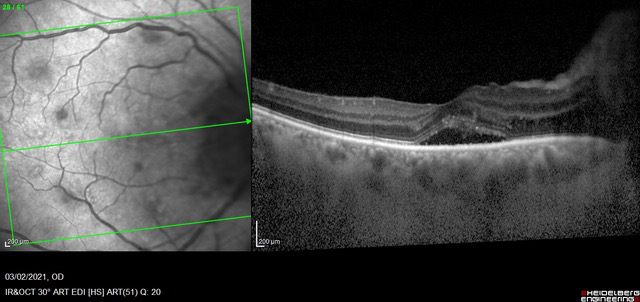

OCT(tomografía de coherencia óptica): la usamos para ver con mayor magnitud detalles de la retina y del nervio óptico, es un estudio que no irradia. No hace falta que la pupila esté dilatada para poder realizarlo.